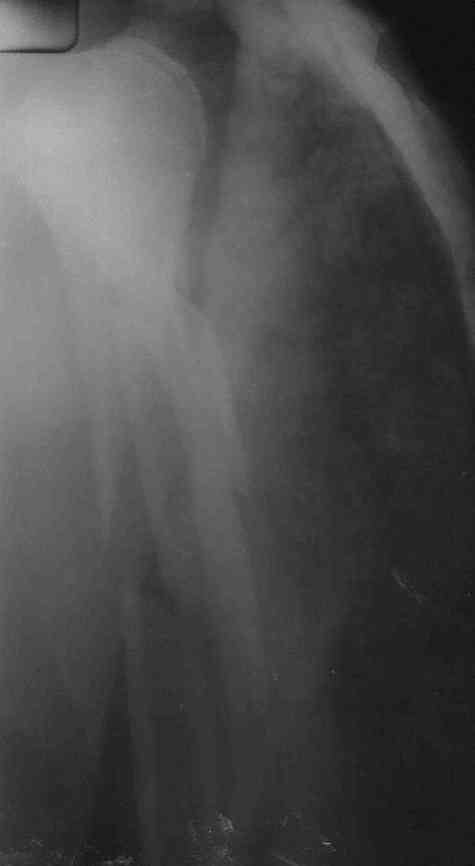

Немножко переделал повязку с отведением, подправил, вот что получилось.

Перелом внутрисуставной, Вы уверены на счет Сармиенто? На первичном снимке не видно было перелома головки.

В наших условиях выбрали бы закрытое штифтование проксимальным гвоздем для плеча T2 Stryker. Голоку предварительно бы фиксировали спицами вне траектории гвоздя, чтобы не разобщить отломки.

Чтобы помочь определиться с выбором, и уточнить особенности выбранного варианта, надо знать, какие варианты доступны на месте.